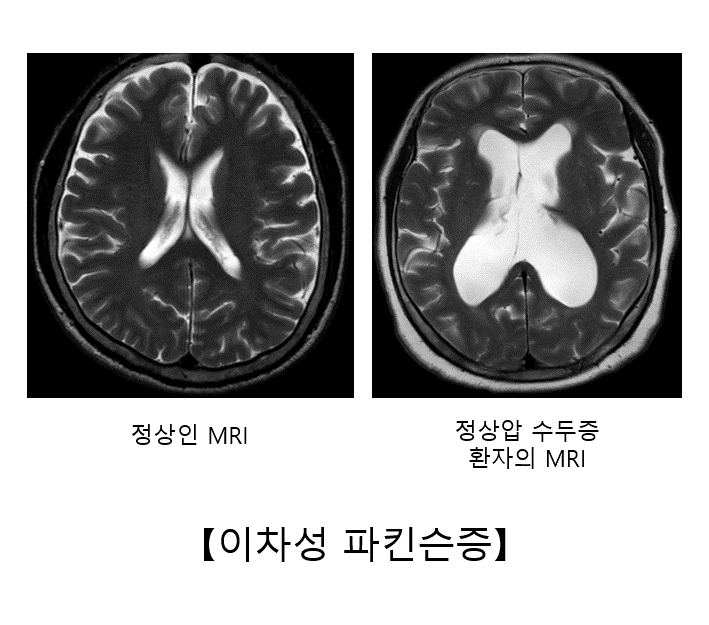

정상압 수두증은 뇌척수액이 원활하게 순환되지 않아 뇌실이 확장되면서 주변 뇌를 압박하여 정상적인 기능에 장애를 초래하는 질환을 말합니다. 정상압 수두증의 가장 주된 증상은 보행 장애입니다. 환자는 발을 넓게 벌리고 종종걸음을 걷습니다. 파킨슨병처럼 운동 완만이나 체위 불안정도 흔하게 나타납니다. 배뇨 장애와 인지 기능의 저하가 동반되는 경우가 많습니다.

정상압 수두증은 뇌 전산화 단층촬영(CT)이나 뇌 자기공명영상(MRI)에서 뇌실이 커져 있는 소견이 확인됩니다. 척수 천자를 통해 뇌척수액을 배액했을 때 일시적으로 파킨슨 증상이 호전되면 진단할 수 있습니다. 이러한 경우 뇌실복강션트라는 수술을 하면 지속적으로 뇌척수액을 배액하여 증상을 호전시킬 수 있습니다.